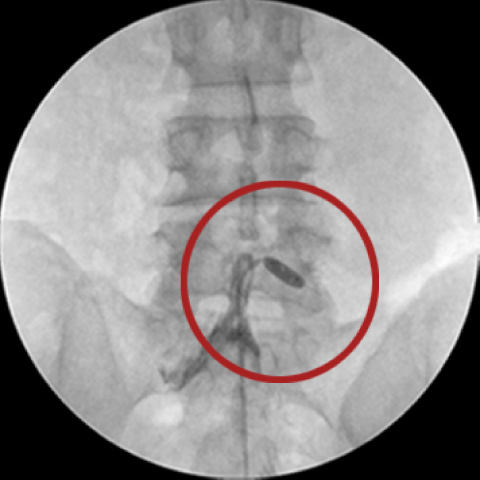

내시경 레이저 디스크 제거술(PELD)

시술과 수술의 중간 정도의 개념으로 직경 1cm 이하의 카메라가 달린 관을 삽입해 화면을 보면서 진행합니다. 1cm 정도의 작은 절개로도 문제 되는 디스크를 제거할 수 있는 시술과 수술의 장점만을 모은 시술법입니다. 수술과 비슷한 방식으로 직접 디스크를 제거하며 압박된 신경이 감압된 것도 확인이 가능합니다.

□ 내시경 화면으로 직접 병변 부위를 보기에 보다 정확하고 안전